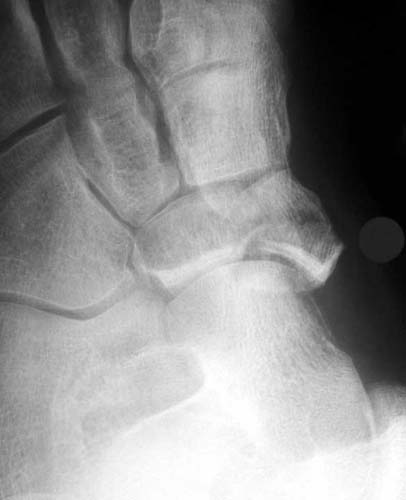

39yo male construction worker presents with 10 day old closed comminuted navicular # following low velocity fall from small motorcross bike.

Any thoughts on management would be appreciated.

Reconstruction vs. ex fix vs. primary graft and fusion.